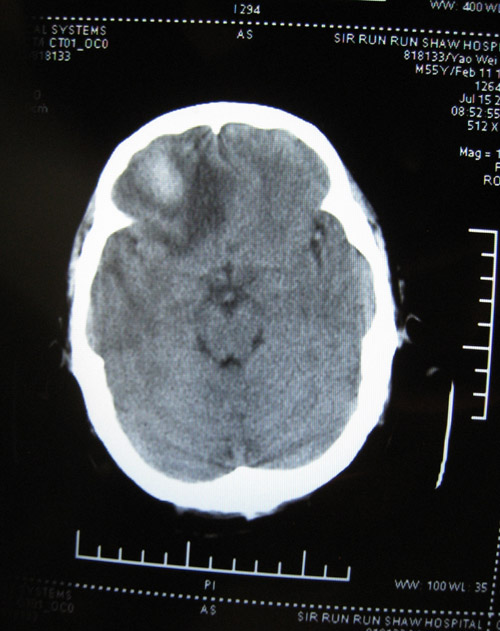

CTʱ¼ä2008-07-15 ÔçÉÏ9µãÖÓ

CT±¨¸æ

ÓÒ²à¶îÒ¶¼ûÇ·¹æÔòÍÅÆ¬ÉÔ¸ßÃܶÈÓ°£¬ÆäÖܱ߼ûƬ״µÍÃܶÈÓ°Ë®Ö×Ó°»·ÈÆ£¬±ß½çÇ·Ç壬¾Ö²¿¿É¼ûռλЧӦ£¬ÓÒ²à¶îò¨Ò¶ÄÔ¹µ±ädz£»ÓàÄÔʵÖÊÄÚδ¼ûÒì³£ÃܶÈÓ°£¬ÖÐÏßÏò×ó²àÒÆÎ»£¬Â¹Çδ¼ûÃ÷ÏÔ¹ÇÕÛ¡£

ÎÊÌâ²¹³ä£ºCTƬ2008-07-15 µÄÓ¡ÏóÊÇ£ºÓÒ²à¶îÒ¶ÄÔ´ìÁÑÉ˰éѪÖ×Ðγɣ¬¶ÔÕÕ08.07.09ƬѪÖ×ÉÔÎüÊÕ£¬Ë®Ö×Ïà·Â¡£